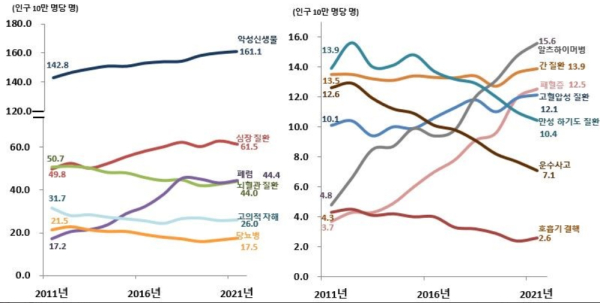

통계청이 발표한 2021년 사망원인통계연보에 따르면 암(악성신생물)으로 인한 사망은 최근 10년간 지속해서 늘고 있다.

인구 10만명당 암 사망자는 2011년 142.8명이던 것이 2021년에는 161.1명으로 크게 증가했다.

심장질환은 2011년 49.8명에서 2021년 61.5명, 폐렴은 2011년 17.2명에서 2021년 44.4명으로 늘었지만 암으로 인한 사망자가 월등히 많은 것을 알 수 있다.